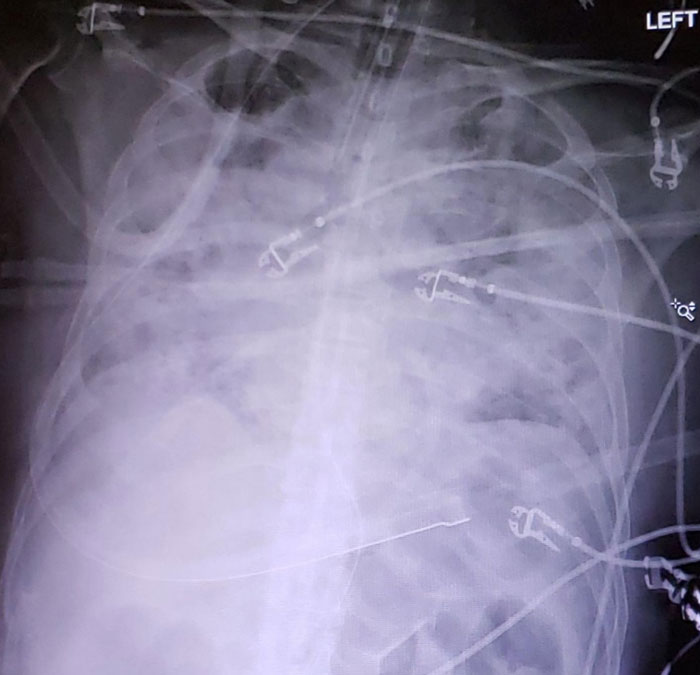

5-Day Progression Of Covid Pneumonia

I Took This X-Ray On A Covid+ Patient Hours After My Friend Tried To Tell Me Covid Isn't That Bad